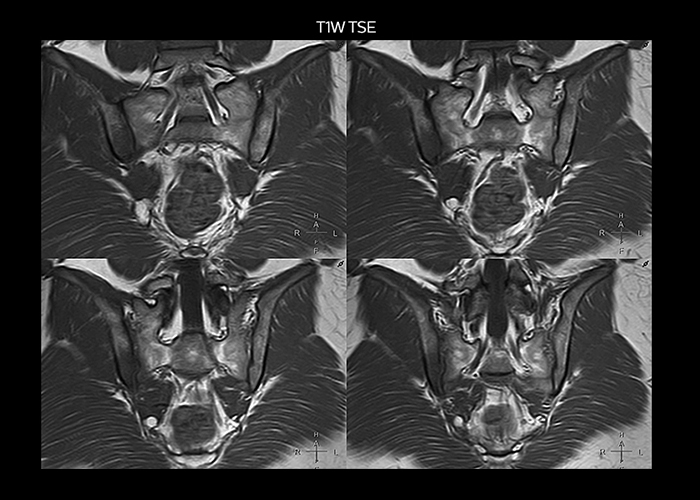

“On average, we scan about 80 patients per day, but on some days we scan well over 100 patients. The scanner is in use 7 days per week, operated 20 hours per day on week days and 8 hours per day in the weekend,” Mr. Tuna says. “To avoid coil changes we plan examinations of similar anatomies back to back, such as head and spine. Multiva helps us here a lot because coils don’t need to be changed frequently. Moreover, thanks to parallel imaging technology and 16-channel HeadSpineTorso and 8-channel MSK coils we are able to achieve excellent image quality. In this way Multiva helped us to increase both image quality and productivity.” “Neurological cases, such as brain and spine imaging, represent the largest share in our MR scanning, followed by musculoskeletal cases. In general, we use simple and basic imaging protocols. But occasionally, we use advanced techniques for problematic cases if necessary.

“Since we have Multiva, we have improved our workflow, because it has been so easy for our operators to learn and use Multiva. Our operators notice that the coils are lightweight and coils don’t need to be changed frequently. The user interface is easy to use. Features like this help us to scan a high number of patients. For instance, the musculoskeletal coils can be used interchangeably, and due to the user-friendly interface, the number of mistakes such as, for example, correct coil element selection has decreased significantly, because the system does it automatically by itself.” “Most important, Multiva satisfies our clinical imaging needs very well,” says Mr. Tuna. “Many features of Multiva have become similar to the Ingenia system. Even in more complex imaging such as abdominal and cardiac, the image quality and performance of Multiva is better than we expected. General surgeons and physicians from our hospital’s internal medicine department prefer to refer to us because of this.”